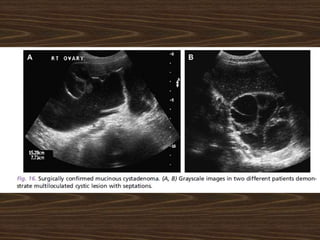

65 year old woman

Year: 1980

Courtesy:

Dr.Jose, General

Surgeon

Tumor: Pseudo

Mucinous

Cystadenoma

Of ovary

Olden days …

65 year oldwoman Year: 1980 Courtesy: Dr.Jose, General Surgeon Tumor: Pseudo Mucinous Cystadenoma Of ovary